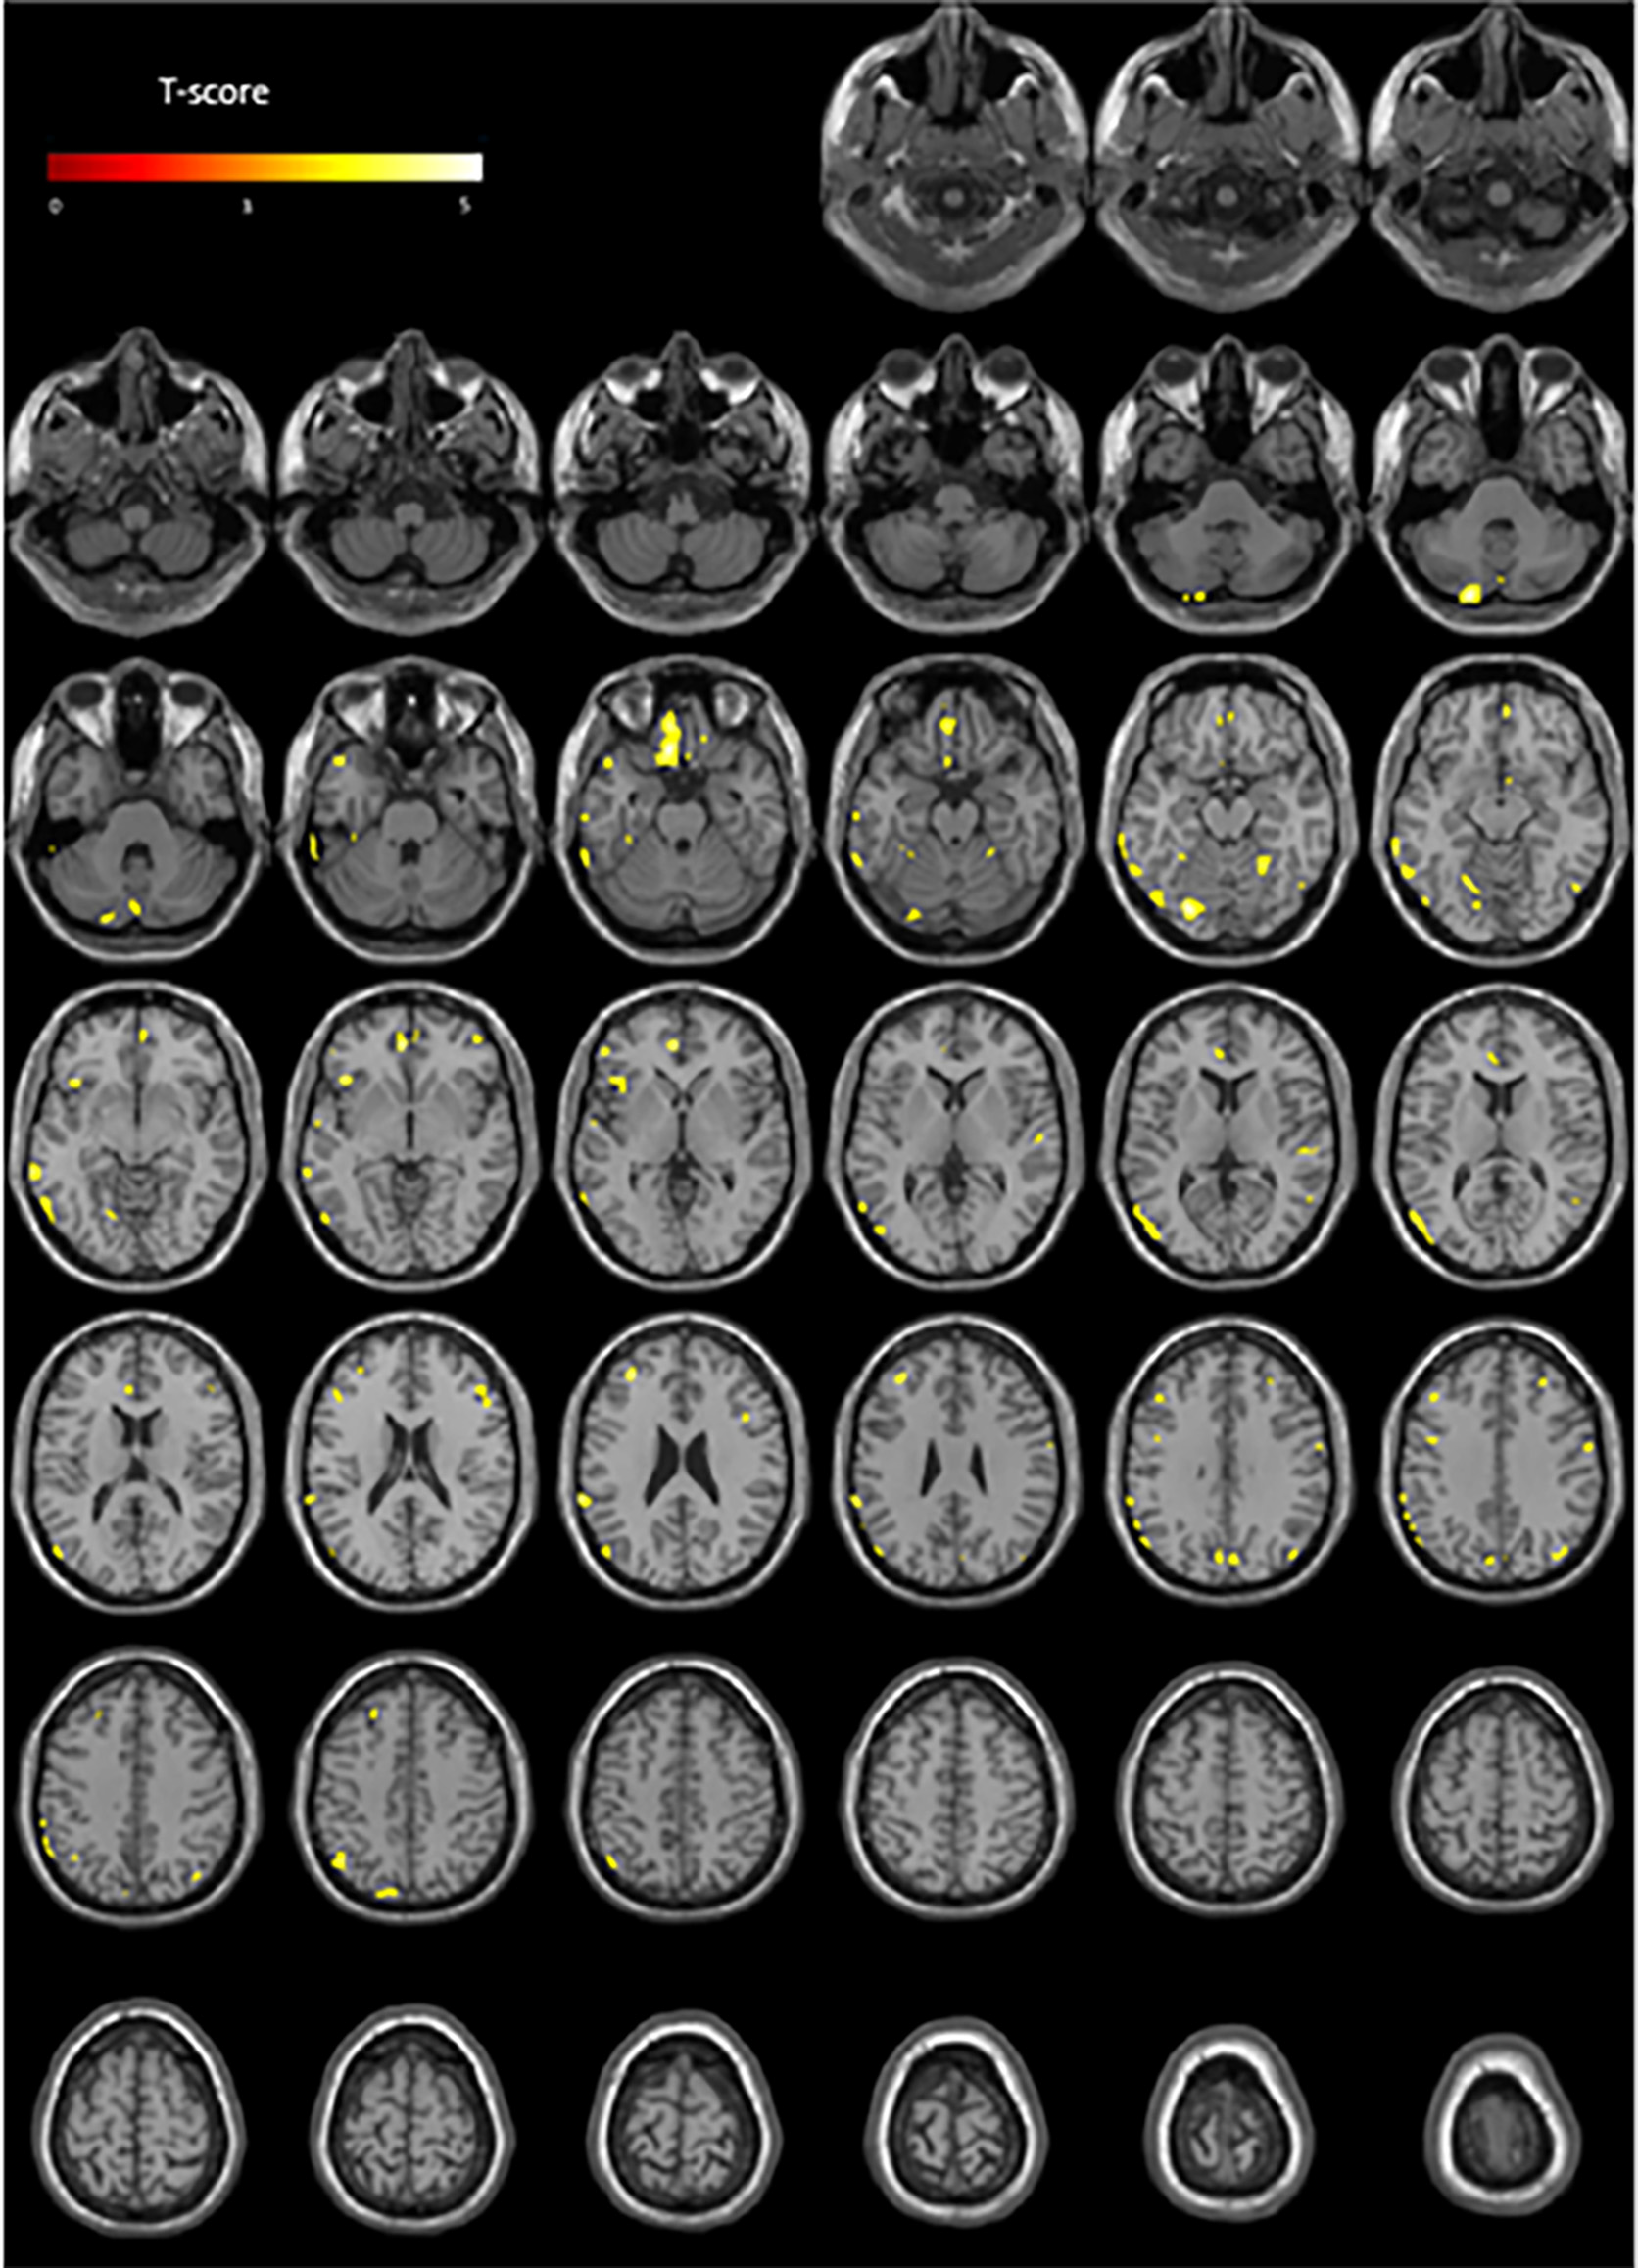

Table 2 summarizes analyses of the whole population. The HR parameter showed the most extensive interactions with cerebral metabolism (37 clusters, cumulative volume of clusters: 15,857 mm3, T-score peak: 5.1) specifically with the frontal (35.8% of cumulative volume) and temporal lobe (33.2% of cumulative volume) regions. The T-maps projected onto two-dimensional slices of axial T1-weighted MRIs are given in Figure 2 and the spatial locations of abnormalities are detailed in the Supplementary Material.

Figure 2

Anatomical localizations of significant brain metabolic clusters associated with HR (negative association) in the whole population (p < 0.001, uncorrected) projected onto two-dimensional slices of T1-weighted MRIs (from the base to the top of the skull).